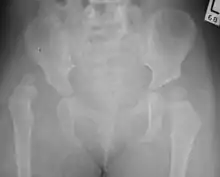

![]() | |

| Congenital dislocation of the left hip in an elderly person. Closed arrow marks the acetabulum, open arrow the femoral head. | |